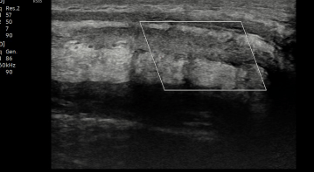

La corporotomía óptica con resección transcorporal es una técnica avanzada que permite la excisión del tejido fibroso bajo visión directa. Esta técnica ofrece un alto nivel de precisión, reduciendo el riesgo de complicaciones. Al realizar el procedimiento bajo visualización directa, el cirujano puede identificar y evitar posibles obstrucciones o irregularidades que podrían interferir con la colocación de la prótesis, optimizando así los resultados .

En los casos en que la fibrosis dificulta la dilatación tradicional de los cuerpos cavernosos, el uso de cavernotomos especializados puede ser de gran ayuda. Estos dispositivos facilitan la expansión del tejido fibrosado, creando un espacio adecuado para la inserción de los cilindros de prótesis inflables. La dilatación con cavernotomos reduce el riesgo de perforación y otros problemas que pueden surgir al tratar de expandir manualmente tejidos muy endurecidos por la fibrosis .

En casos de fibrosis severa donde la contractura de la túnica albugínea limita el espacio, se puede realizar una reconstrucción corporal simultánea con la implantación de una prótesis peneana. Debido a la restricción del tejido, es posible que se deba optar por cilindros de prótesis de tamaño reducido, adaptados a las características anatómicas del paciente y al espacio disponible después de la resección del tejido fibroso .